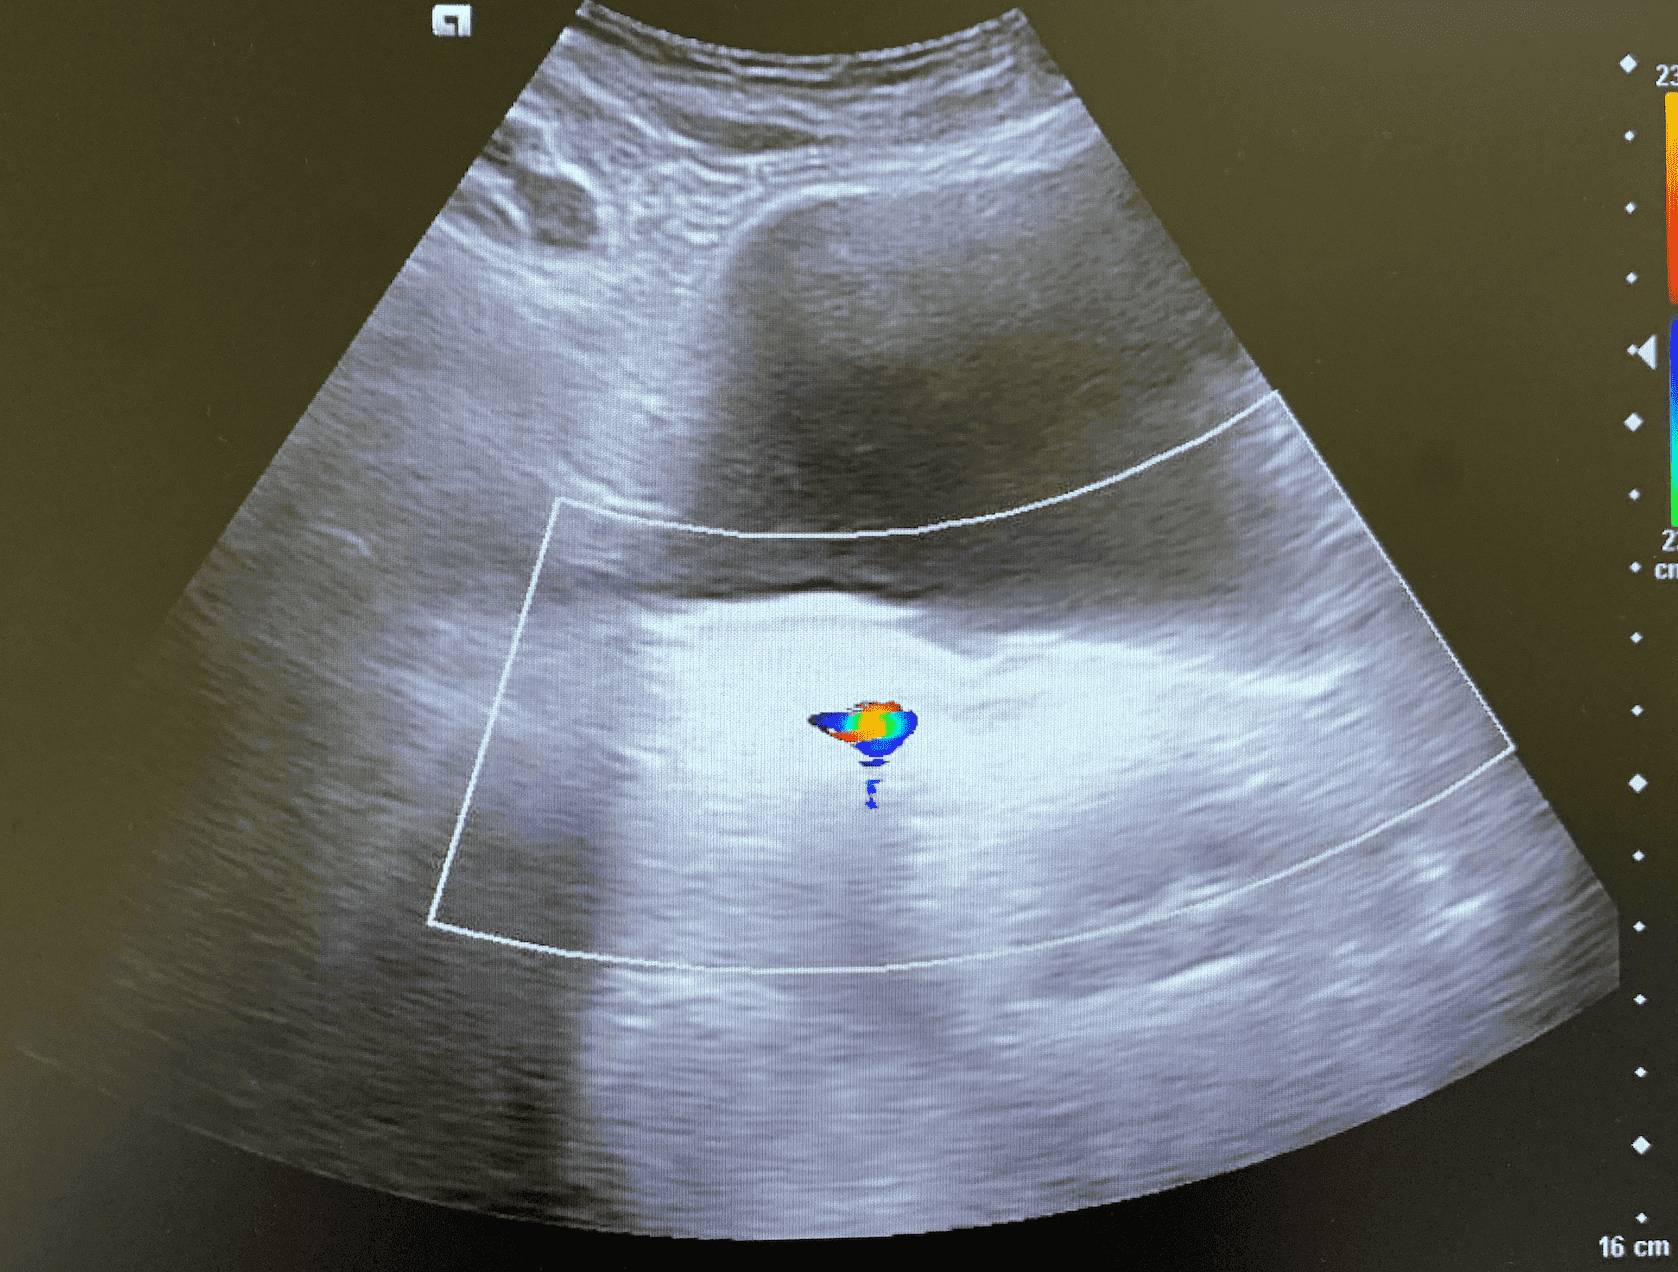

Vejiga repleccionada de paredes lisas, sin evidencia de crecimiento en su interior. Visualización de ambos jets ureterales. Se observa fenómeno de centelleo en trayecto ureteral derecho, sugestivo de litiasis.

Realizamos nueva ecografía, desapareciendo fenómeno de centelleo. Resto de exploración ecográfica nefrourológica normal.

El uso de Doppler color nos ayuda a detectar cálculos pequeños de difícil visualización gracias al artefacto de centelleo. Consiste en una rápida alternancia del color inmediatamente detrás de un objeto ecogénico, dándose una falsa apariencia de movimiento.